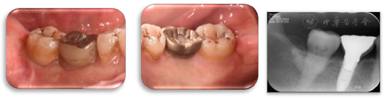

术后6年,47牙龈无明显红肿,远中及颊侧中央PD 3~4 mm,颊侧退缩根面得到覆盖,颊侧中央出现附着龈,宽约2 mm,BI1,X线片示远中骨缺损明显修复(图25,图26,图27),CBCT示47颊侧骨缺损深约4 mm,宽约1.5 mm,远中骨缺损深约5 mm,宽约3 mm,较初诊时颊侧及远中骨缺损均得到明显修复且骨高度保持稳定(图28,图29)。